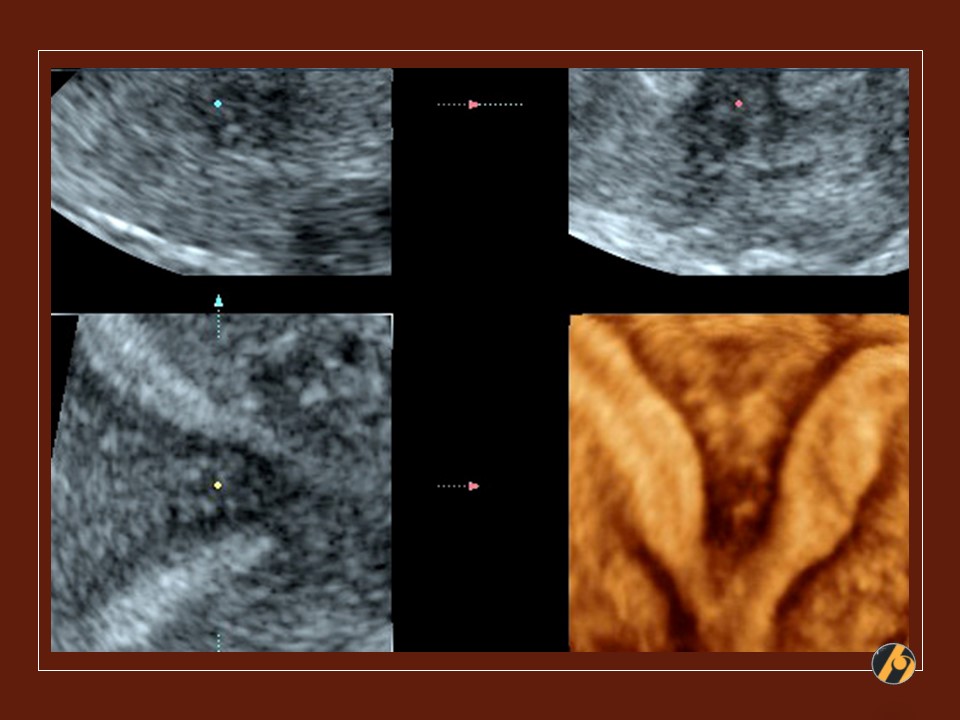

3D ultrazvuk / Multiplanarni prikaz

3D prikaz maternice u 3 ravnine, kao i rekonstrukcija slike maternične šupljine. Maternična šupljina / kavum maternice, ali i vrat maternice / cerviks podijeljeni su oštrim septumom u dva potpuno odvojena dijela, pri čemu je fundus zaravnjen. Zaravnjen fundus je ultrazvučna potvrda septirane / pregrađene maternice. U ovom slučaju je nužna operativna histeroskopija i resekcija septuma prije planiranja trudnoće, pošto su otežani zanošenje i iznošenje trudnoće. Češći su spontani pobačaji i prijevremeni porod.